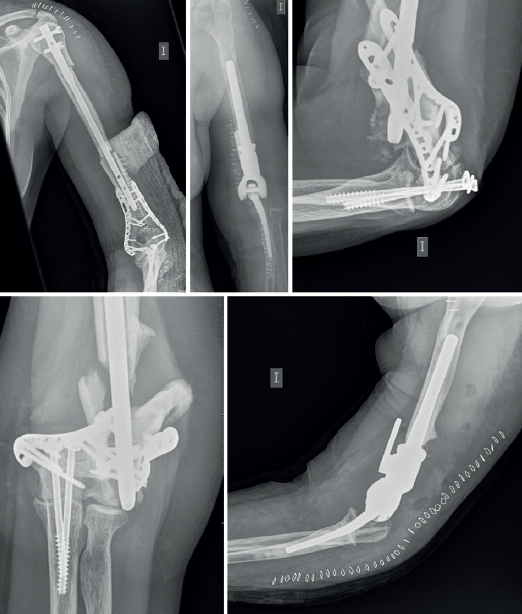

En cuanto a la existencia de pseudoartrosis como en el caso de la Figura 4, hemos adoptado un algoritmo para ayudar en las decisiones de tratamiento relacionadas con las pseudoartrosis y las malas uniones del húmero distal (Figura 5). En este algoritmo hay preguntas clave que deben responderse antes de realizar una revisión con RAFI versus PTCodo y se relacionan con la superficie articular, la viabilidad de los fragmentos y la congruencia de la articulación. Si la restauración de la articulación es imposible, se emplea una PTCodo y los cirujanos deben sentirse cómodos tanto con la fijación como con el reemplazo. En general, como se ha comentado, el área supracondílea es la ubicación típica en la que se producen las malas uniones y las pseudoartrosis. Esto probablemente se deba al micromovimiento en los extremos de la fractura con poca área de contacto hueso con hueso y, en última instancia, a un fallo de la fijación. El área supracondílea debe comprimirse y mantenerse rígida para que cicatrice correctamente. La estrategia en las pseudoartrosis implica 4 principios clave: placas paralelas, acortamiento supracondíleo, autoinjerto de cresta ilíaca y liberación de la contractura. Los resultados después de este enfoque pueden lograr una alta tasa de unión con una función aceptable. De hecho, Donders et al. observaron la curación en 61/62 codos con esta estrategia, aunque el arco de movimiento se vio afectado con un arco promedio de 86(69). Ring et al. observaron la curación en 12 de 15 codos también, siendo la rigidez y los síntomas nerviosos las complicaciones más comunes(70). Como la rigidez es común dado el movimiento a través del sitio de la fractura en lugar de en la articulación, la liberación de la contractura es de suma importancia en el momento de la revisión. Además de un mejor movimiento, la liberación disminuye las fuerzas transmitidas al sitio de la fractura durante la curación.